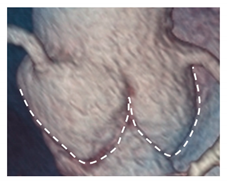

| Aortic annulus | The aortic annulus is the three-dimensional line that follows the hinge line of the leaflets on the aortic wall. This line of dense connective tissue has a crown-shaped appearance (white dotted line). | ![]() |